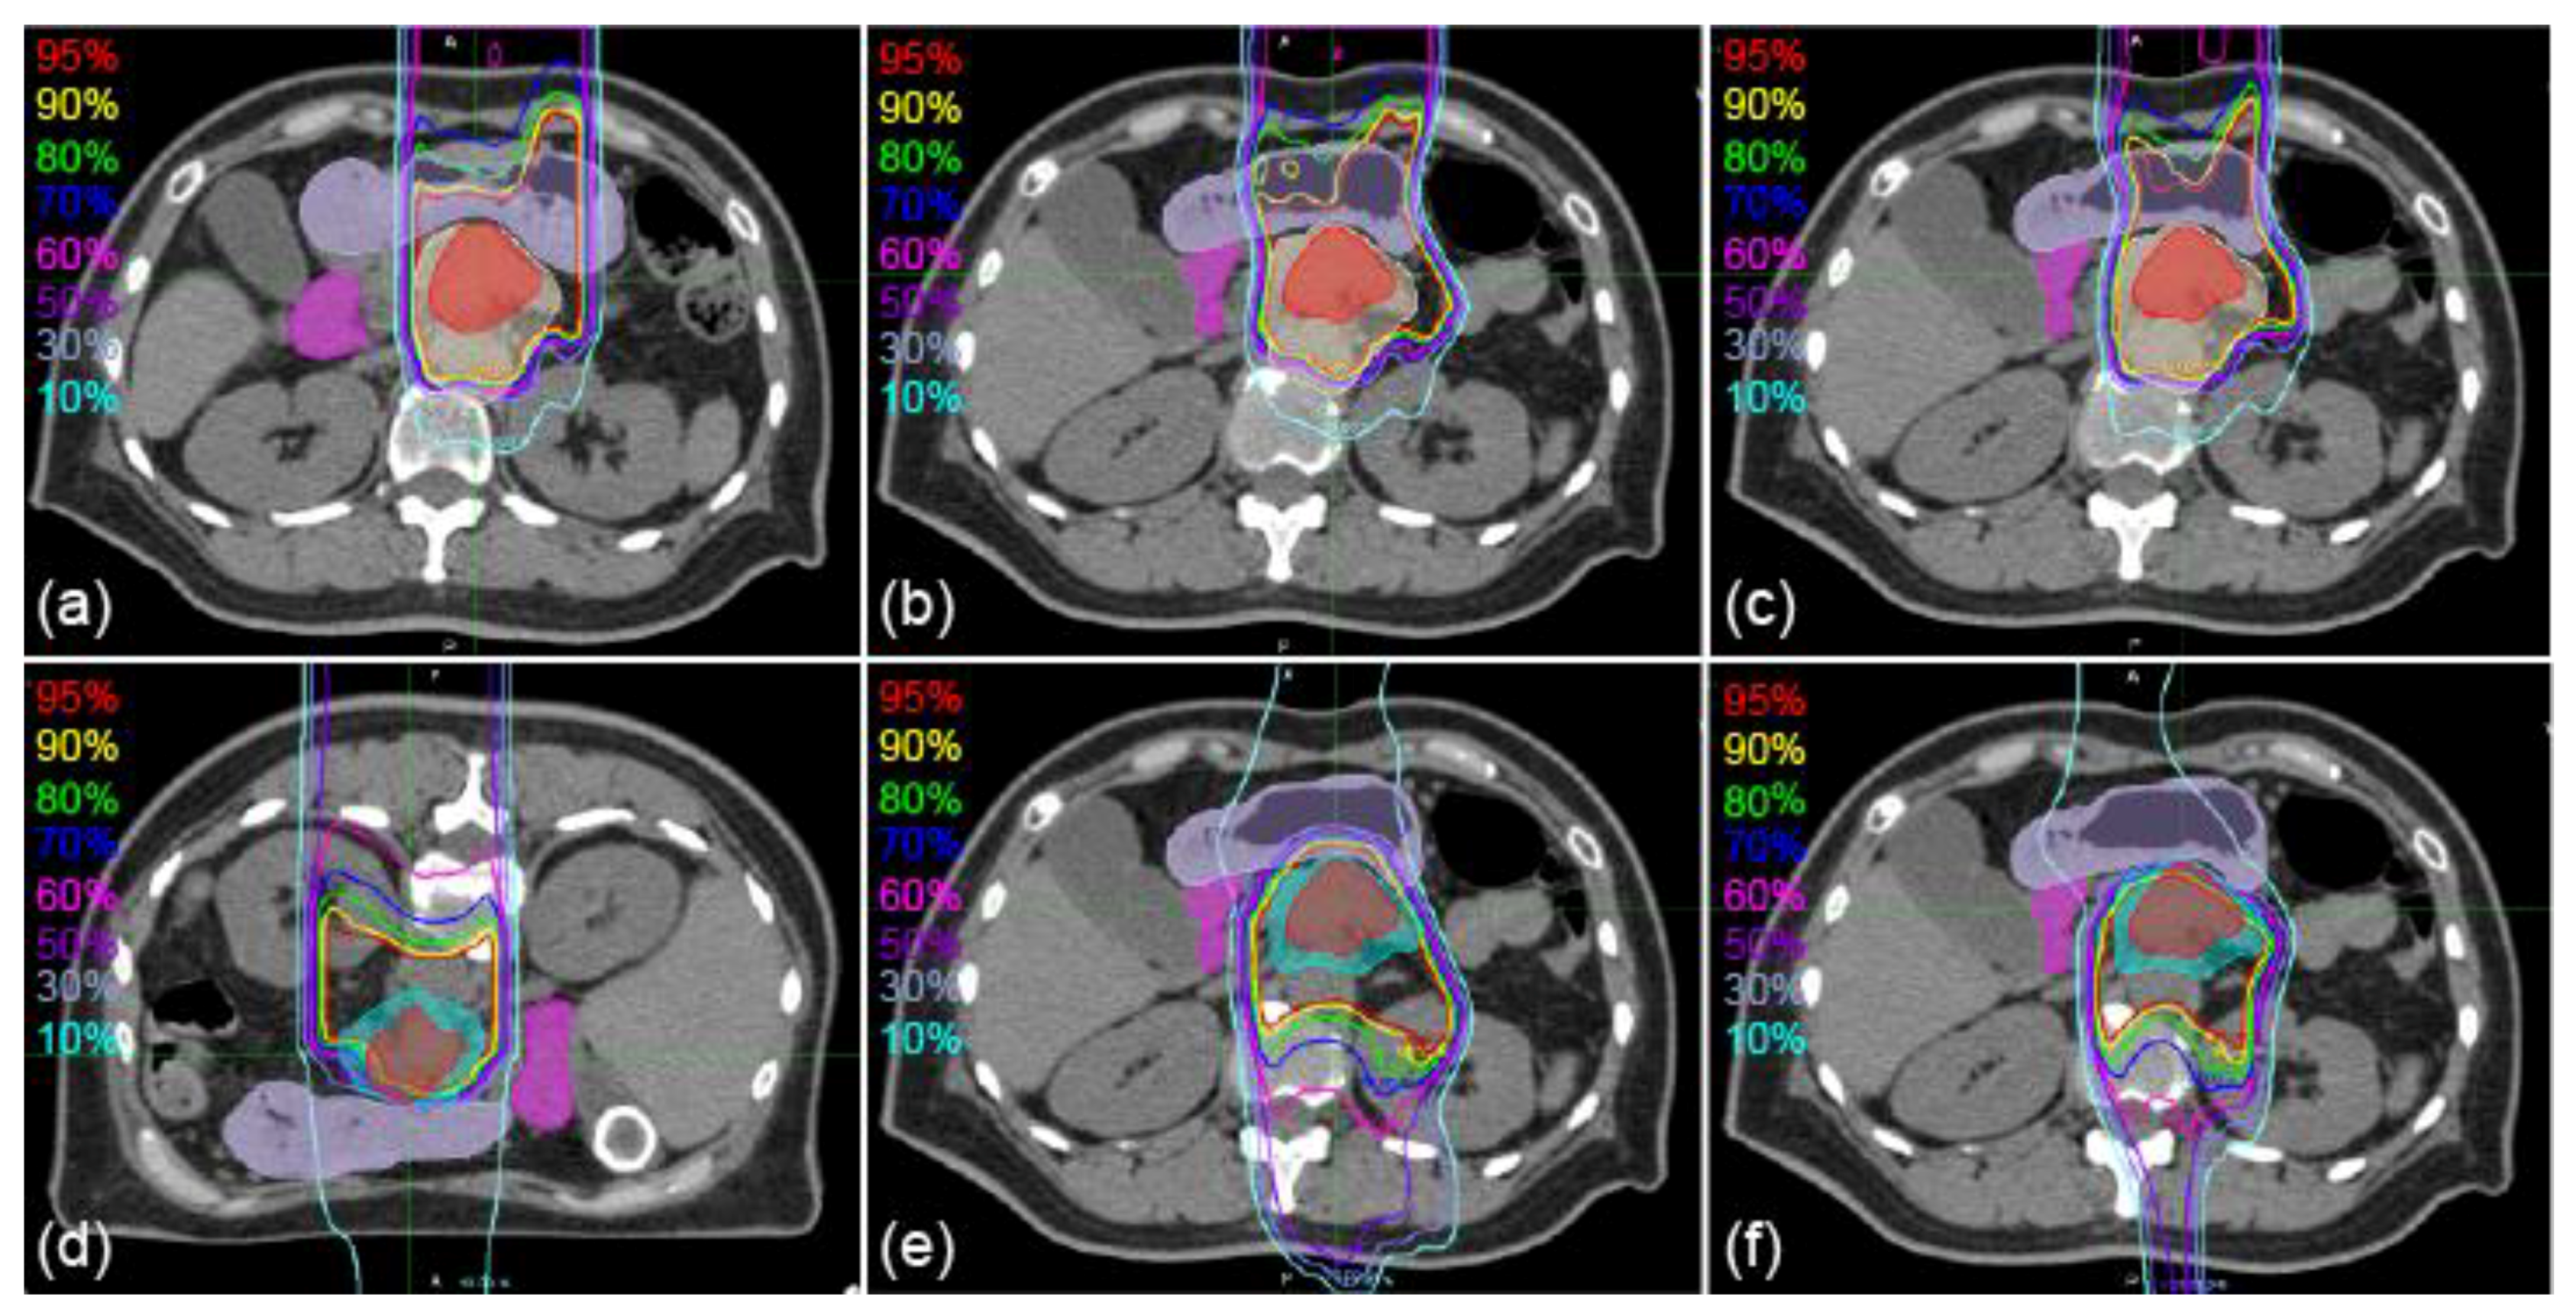

2. Results

Sample CT images with transferred contours and dose distributions of supine and prone positions are shown in Figure 1 and Figure 2, respectively. The dice similarity coefficient (DSC) and mean displacement to agreement (MDA) for each contour for all patterns are shown in Figure 3. In all cases, the means ± standard deviation of the DSCs of all contours (n = 72) were 0.72 ± 0.20, 0.81 ± 0.16, 0.86 ± 0.11, and 0.87 ± 0.08 with RIR, intensity-based DIR (iDIR), contour-based DIR (cDIR), and hybrid iDIR-cDIR (hDIR), respectively; the means ± standard deviation of the MDAs were 3.40 ± 3.30, 2.21 ± 2.48, 1.46 ± 1.49, and 1.46 ± 1.37, respectively. There were significant differences between RIR and the other registration methods for both the DSCs and MDAs (p < 0.001 for all combinations). Moreover, the DSCs and MDAs of cDIR and hDIR were significantly better than those of RIR and iDIR (for both DSCs and MDAs, p < 0.001 for cDIR vs. RIR, and hDIR vs. RIR). For registration from the first irradiation day (1st-IRCT) to the supine position CT images for treatment planning (SP-PlanCT) (SP-SP) cases, the MDAs were less than 2 mm in 45.8% of RIR cases, 83.3% of iDIR cases, 100% of cDIR cases, and 95.8% of hDIR cases. The corresponding values for registration from the 10th-IRCT to the prone position CT images for treatment planning (PR-PlanCT) (PR-PR) cases were 54.2%, 79.2%, 95.8%, and 91.7%, respectively, while for registration from the PR-PlanCT to the SP-PlanCT (SP-PR) cases they were 37.5%, 33.3%, 54.2%, and 54.2%. Differences in the dose-volume parameters for all patterns are shown in Table 1. In all cases, the median differences for (clinical target volume (CTV) V95 were 2.47%, 1.65%, 2.24%, and 1.50% for RIR, iDIR, cDIR, and hDIR, respectively; for gross tumor volume (GTV) V95 the corresponding values were 0.84%, 0.81%, 2.47%, and 1.59%; for stomach V50 they were 1.60%, 2.94%, 0.85%, and 7.56%; and for duodenum V50 they were 0.68%, 0.91%, 0.58%, and 0.68%. Graphs showing the correlations between MDA and DSC, and between MDA and dose-volume parameters, are shown in Figure 4. The correlation coefficients R between MDA and DSC were 0.92, 0.93, 0.91, and 0.84 for RIR, iDIR, cDIR, and hDIR, respectively; the corresponding values between MDA and target (CTV and GTV) V95 were 0.47, 0.65, 0.56, and 0.40; and between MDA and organs at risk (OAR) (stomach and duodenum) V50 they were 0.01, 0.29, 0.23, and 0.44.

The accuracy of DIR was better than that of RIR in cases with the same patient position, while the accuracies of cDIR and hDIR for the CTV, stomach, and duodenum were better than those of iDIR in all patient positions, as shown in Figure 3. Meanwhile, for the GTV, the accuracy of iDIR was better than the other methods. We assume that iDIR is effective when deformations are small and the boundary of the contour is clear. However, we assume that iDIR is not effective when the boundary of the contour is unclear (such as with the CTV), because obtaining pixel-by-pixel correspondence is difficult, which is also the case when CT values show large differences due to changes in gas content (such as in stomach and duodenum). Because cDIR and hDIR are less affected by the above effects, they were better than iDIR for the CTV, stomach, and duodenum.

Figure 3. Registration errors using contours. All graphs show mean ± standard deviation. White, light-gray, dark-gray, and black bars show rigid image registration (RIR), iDIR, cDIR, and hybrid iDIR-cDIR (hDIR), respectively. (ad) show the MDA for each contour, and (eh) show the dice similarity coefficient (DSC) for each contour. (a,e) SP-SP cases. (b,f) SP-PR cases. (c,g) SP-PR cases. (d,h) all cases. *, †, ‡, §, and || indicate significant differences between RIR and iDIR, RIR and cDIR, RIR and hDIR, iDIR and cDIR, and iDIR and hDIR, respectively.